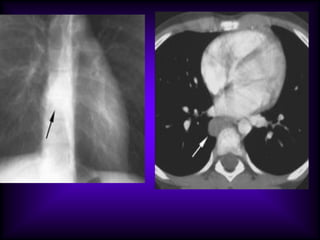

•A central portion  necrosis and communicate to bronchus.

•The draining bronchus is visible (arrow). CT (2 mm slice thickness)

shows discrete air bronchograms in the consolidated area.